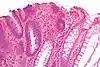

| Type de polype | Apparence histologique | Risque de malignité | Coupe histologique | Syndromes | |

|---|---|---|---|---|---|

| Hyperplasique | Cryptes dentées non-ramifiées | Non |  | Hyperplasique polypose syndrome | |

| Adénome dentelé sessile | Semblable à hyperplasique avec hyperserration, bases des cryptes dilatées/ramifiées, des cellules de mucine apparents à la base des cryptes | Oui |  | ||

| Inflammatoire | Muqueuse/sous-muqueuse élevées avec inflammation | Si développement d'une dysplasie | Maladies inflammatoires chroniques intestinales, ulcères, infections, prolapsus muqueux | ||

| Adénome tubulaire (villositaire, tubulovilleux) | Glandes tubulaires avec des noyaux allongés (au moins à faible teneur atypie) | Oui |  | ||

| Adénome dentelé traditionnel | Cryptes dentelées, souvent une structure villeuse, avec atypie cytologique, des cellules éosinophiles | Oui |  | ||

| Polype de Peutz-Jeghers | Faisceaux musculaires lisses entre l'épithélium non-néoplasique, apparence d'« arbre de Noël » | Non |  | Syndrome de Peutz-Jeghers | |

| Polype juvénile | Glandes kystiques dilatées avec la lamina propria élargie | Non intrinsèquement, peut développer une dysplasie |  | Syndrome de polypose juvénile, polypes identiques que dans le syndrome de Cronkhite-Canada | |

| Polype hamartomateux | Variable ; polype classique légèrement fibreux avec la muqueuse désorganisée et écartement des muscularis mucosae ; aussi inflammatoire, juvénile, lipome, ganglioneurome, lymphoïde | Non | Maladie de Cowden | ||

| Polype fibroïde inflammatoire | Cellules en fuseau avec des amas concentriques de cellules fusiformes autour des vaisseaux sanguins et l'inflammation riche en éosinophiles | Non |  | ||